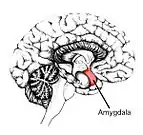

Les voies auditives non classiques fournissant une voie sous-corticale à l'amygdale peuvent être impliqués dans la phonophobie[2].